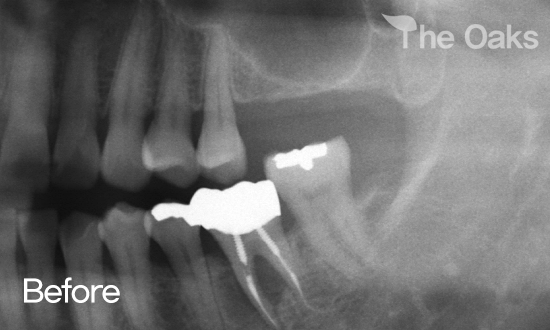

ÀÓÇöõÆ® Ä¡·á¸¦ ¹ÞÀ¸½Å Á¤OO´Ô ÀüÈÄ»çÁø°ú ÈıâÀÔ´Ï´Ù.

50´ë ÈĹÝÀÇ ³²¼º ȯÀÚºÐÀ̽ðí, Ä¡·á Àü ÀÕ¸ö¿°ÁõÀ¸·Î ÀÎÇÑ Ä¡¾Æ Èçµé¸²À¸·Î ³»¿øÇϽŠÄÉÀ̽ºÀÔ´Ï´Ù.

¿°Áõ ¹®Á¦·Î »À¼Ò½ÇÀÌ Å« °ü°è·Î »ÀÀÌ½Ä ÈÄ º¯È­¸¦ üũÇÏ¿´°í,  ¼ö¼ú¿¡ ÀûÇÕÇÑ »óÅ¿¡¼­ ÀÓÇöõÆ® ¼ö¼úÀ» ÁøÇàÇÏ¿´½À´Ï´Ù.

¾ÈÁ¤ÀûÀ̰í Á¤È®ÇÑ º¸Ã¶¹° ½Ä¸³ ÀÌÈÄ ÇöÀç±îÁöµµ ȯÀںв²¼­ ÃæºÐÈ÷ ¸¸Á·½º·´°í µçµçÇÏ°Ô »ç¿ëÇÏ°í °è½Ê´Ï´Ù.